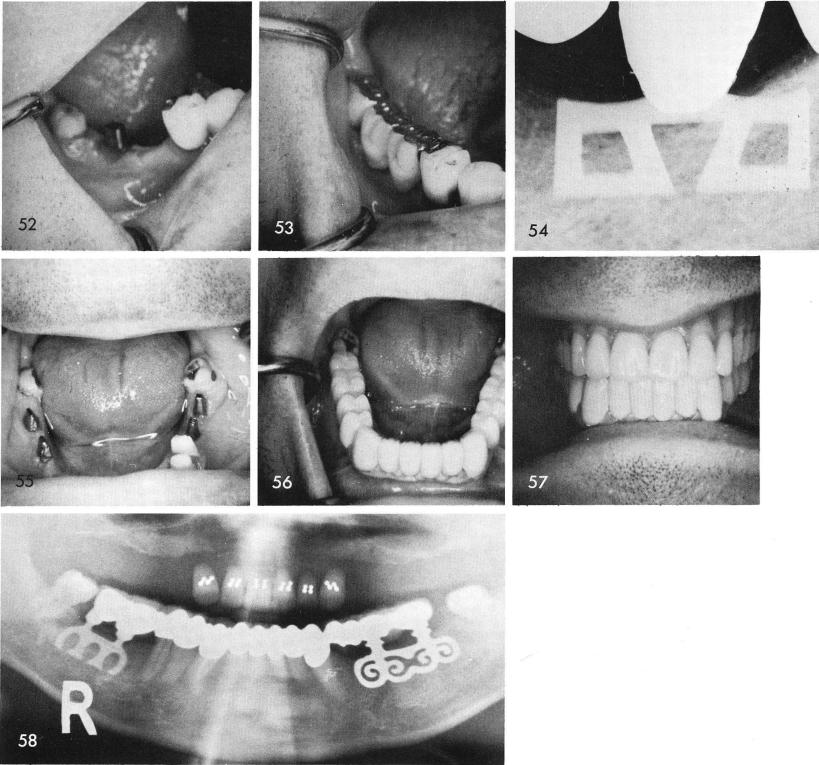

the blade, when tapped into position, figs. 50, 51, 52, will have its head fit directly into the hole made in the prefabricated bridge, fig. 53. A post-operative periapical film, fig. 54.

There are times when even though the blades are in between teeth mesially and distally, due to excessive tipping of the posterior teeth, the blades are not splinted to them, fig. 55. The final restorations are supported anteriorly with natural teeth and posteriorly by the blades, figs. 56, 57, 58.